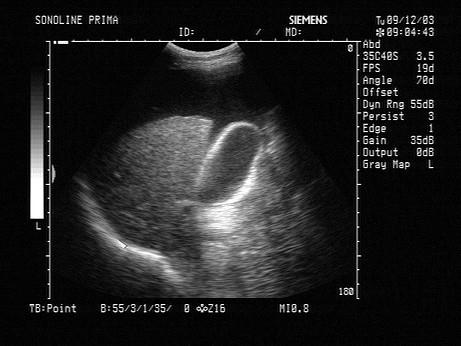

根据声像图表现,诊断是?(?)A.胸水B.腹水C.正常D.肠梗阻E.胆囊

问题 根据声像图表现,诊断是?(?)

选项 A.胸水 B.腹水 C.正常 D.肠梗阻 E.胆囊

答案 B